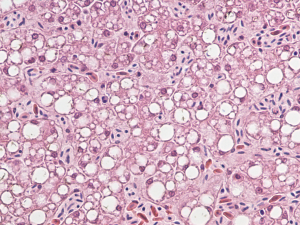

Officials at the USGS National Wildlife Health Center conducted necropsies to determine the cause of death and found liver damage in most of the birds. Damage to brain tissue was also common. Searches for environmental toxins underlying the disease came up empty.

“It is curious that the liver pathology of the eagles resembles the damage to human livers caused by hepaciviruses,” says White, branch chief for wildlife epidemiology and emerging diseases at the USGS National Wildlife Health Center. “But since the lesions are nonspecific there’s more that needs to be explored if we want to understand the virus itself or really get at what is the cause of WRES.”